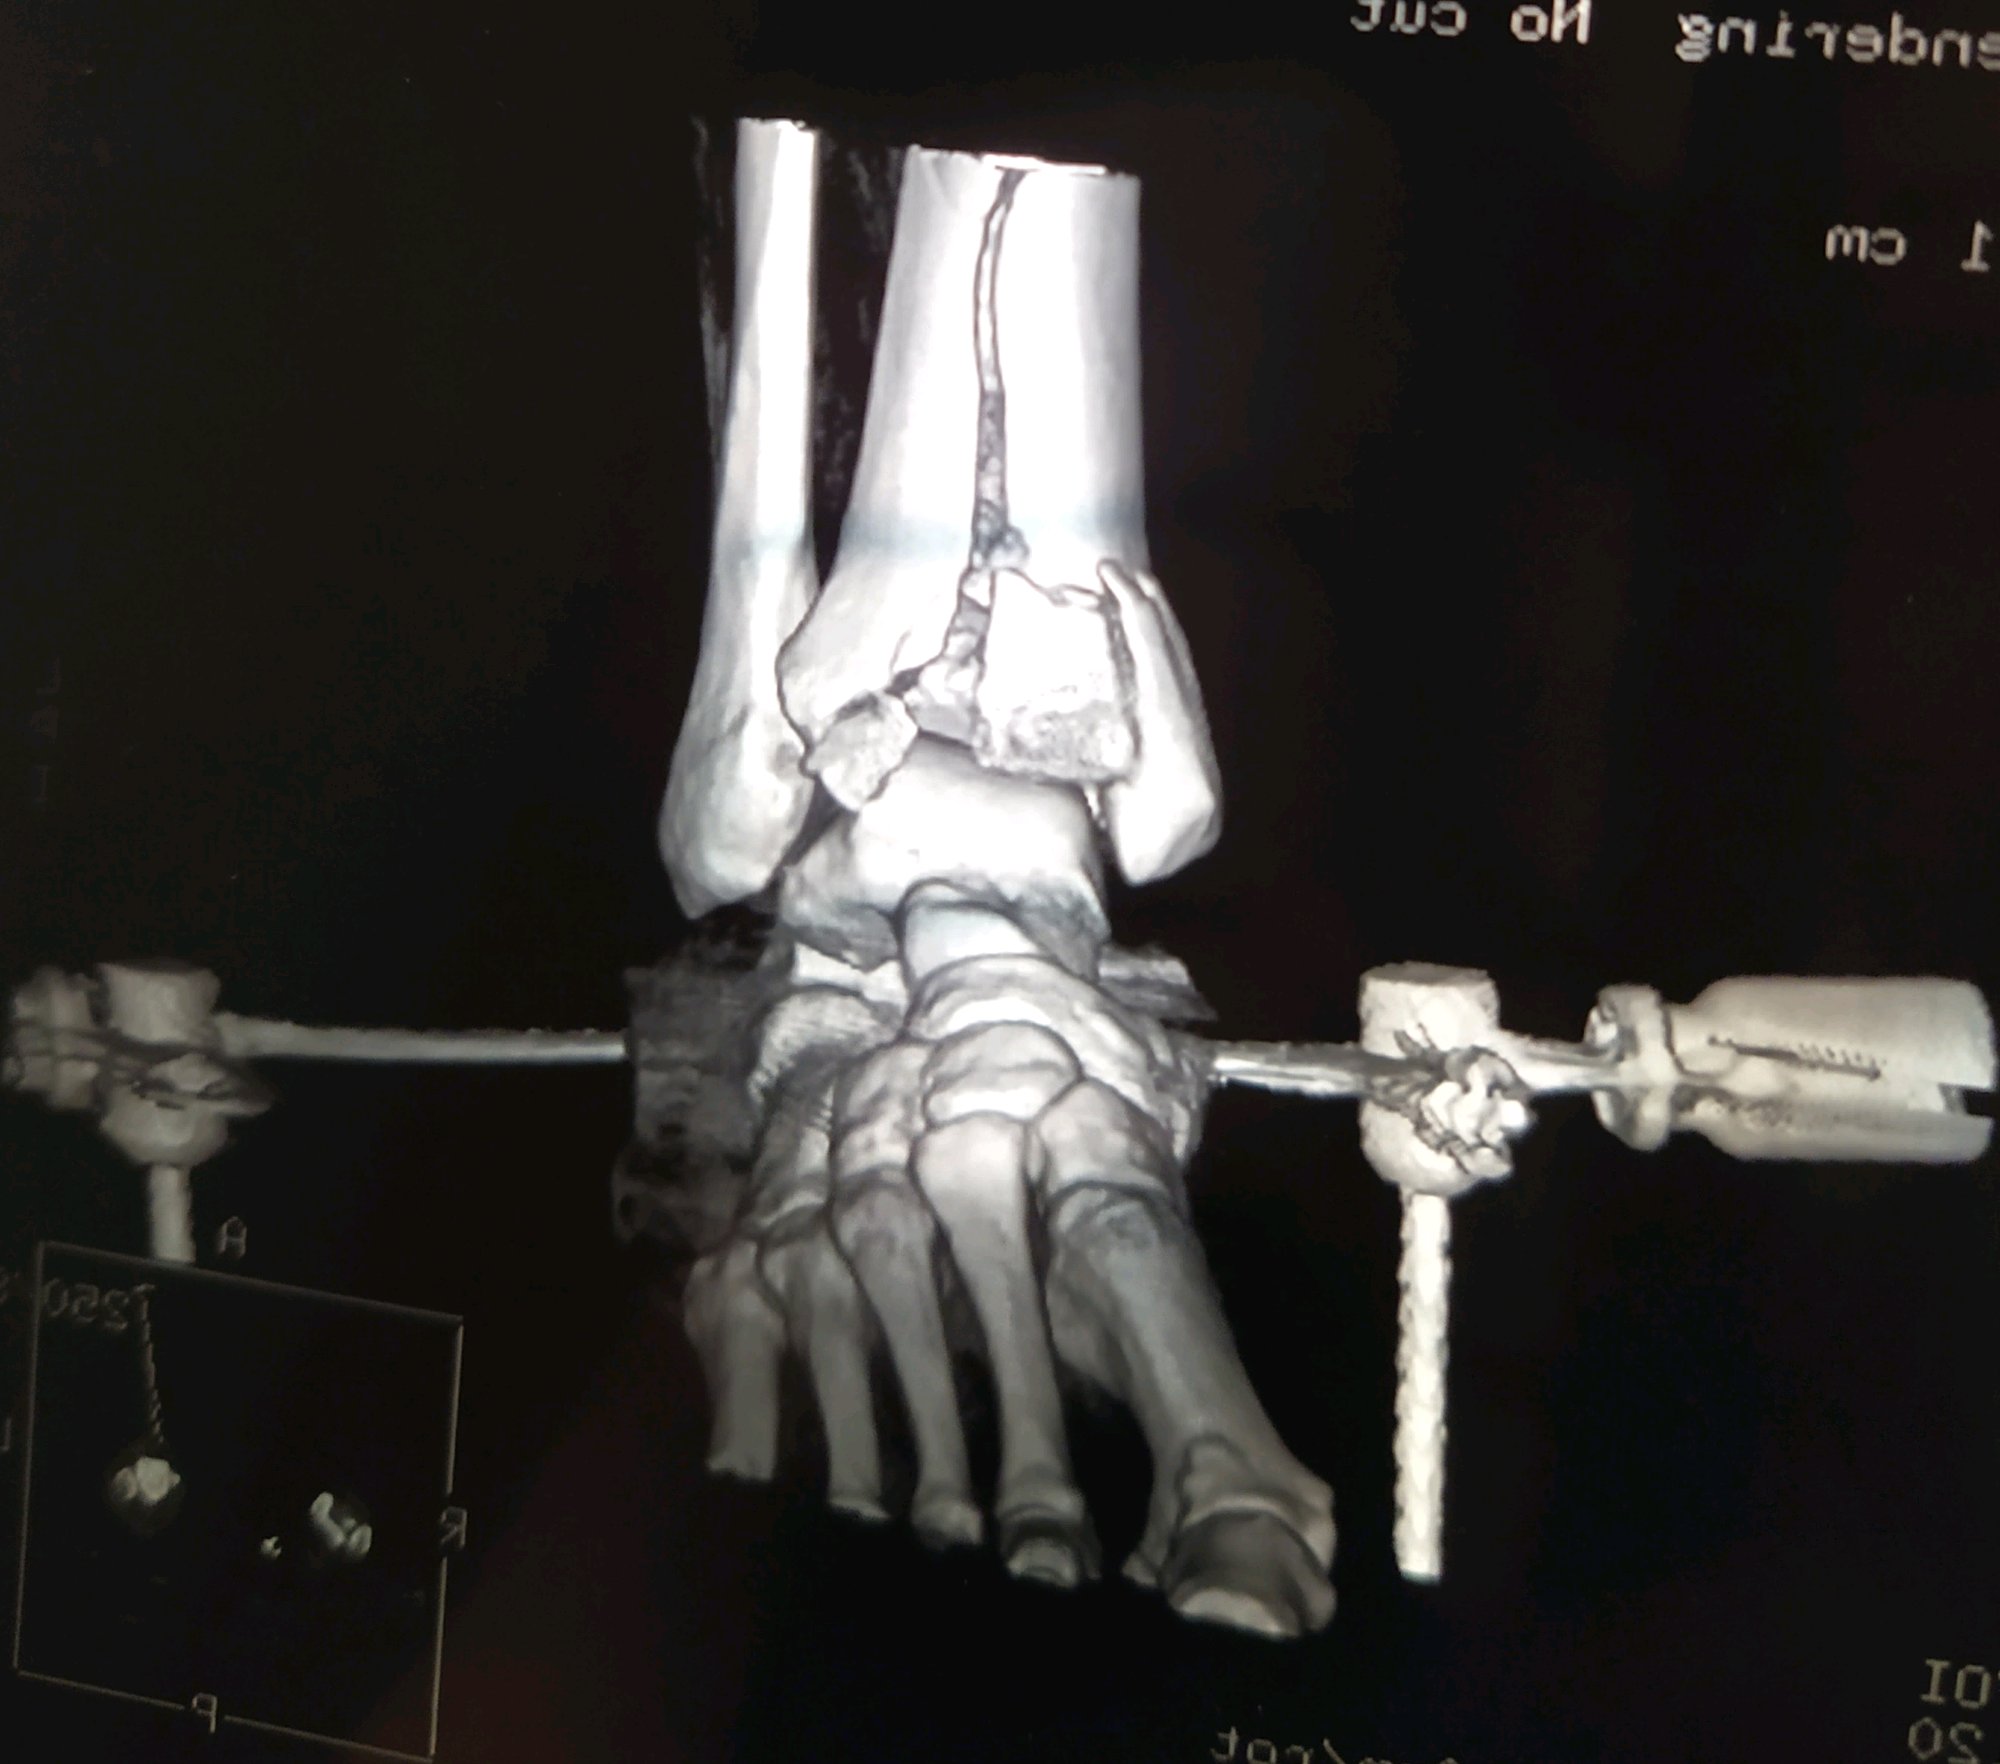

江苏扬州,男,43岁,月薪1w,工伤认定已完成。请问估计能定几级伤残,大概能赔偿多少?